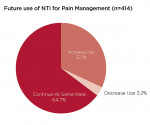

Four hundred and fourteen providers responded to a question about future use of the nociceptive trigeminal inhibition splint for pain management. They were queried about whether they planned to continue using the NTI for pain management at the same rate as in recent years, or planned to increase or decrease its use. Thirty-two percent (n = 133) stated they would increase their use for this indication (Figure 6). Approximately 97% stated they would maintain (n = 268) or increase (n = 133) their levels of NTI use. Of 511 responses to a question regarding fabrication techniques, 34% (n = 172) exclusively use direct fabrication, 31% (n = 160) use the laboratory-fabricated method, and 35% (n = 179) use both methods. The number of patients reported to have developed a clinical observation of an anterior open bite subsequent to use of the device was reported as 1.6% of 78,711 cases (Figure 7). Of patients reporting aspiration of the device (0.3%), no events were documented by radiograph or other means.